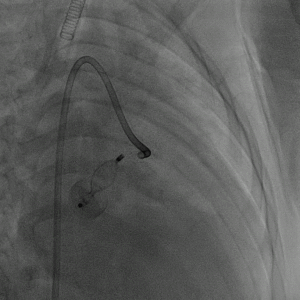

术后造影示栓塞处少量穿伞分流,前降支通畅,冠状静脉窦通畅。

图片

术后一月后心脏彩超:冠状静脉窦(邻近右房入口处)内探及封堵器回声,位置固定。回旋支-冠状静脉窦封堵器周未见明显分流。